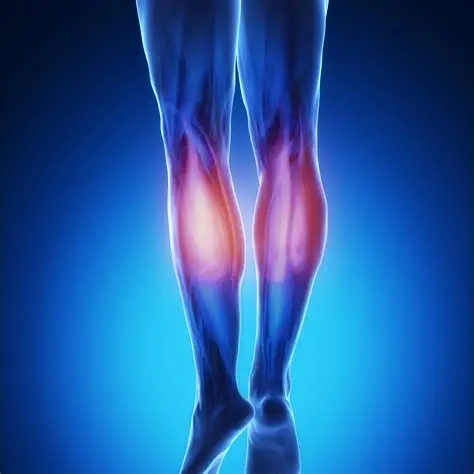

Gastrocnemius Rupture